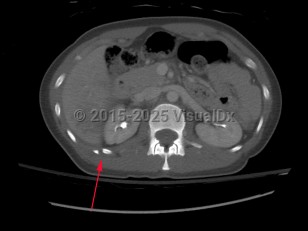

Imaging Studies image of Rib fracture - imageId=7885255. Click to open in gallery.  caption: '<span>CT scan of the chest in bone windows demonstrating fractures of the right 11th and 12th ribs.</span>'

CT scan of the chest in bone windows demonstrating fractures of the right 11th and 12th ribs.